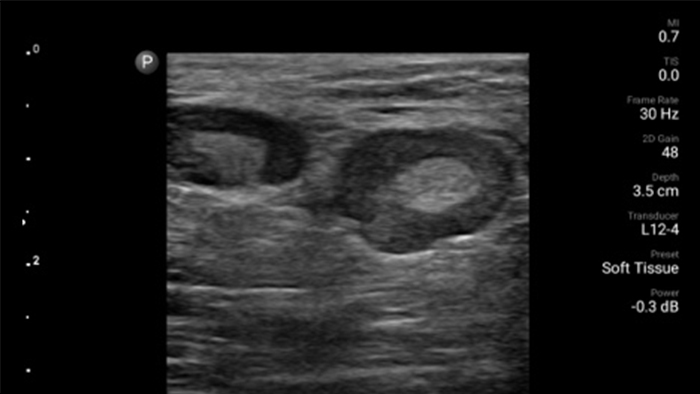

De Lumify draagbare echografieoplossing voor loco regionale anesthesiologie helpt u bij het visualiseren van de omliggende zenuwen, vaten, omliggende weefsels en naald-in situ tijdens de procedure.

Lumify helpt u de plaatsing van de naalden, de omringende zenuwen, vaten en fascia-vlakken duidelijk te visualiseren.

Lumify kan helpen de subtiele details van een beeld zichtbaar te maken en afwijkende weefselstructuren bloot te leggen vanuit verschillende hoeken. Hierdoor kunt u met vertrouwen realtime beslissingen nemen, van diagnose tot herstel.